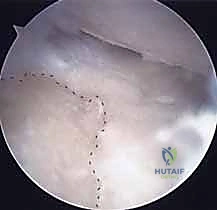

| الرؤية الجراحية | رؤية مباشرة وممتازة للأربطة والعظام | رؤية مكبرة من الداخل عبر الكاميرا |

| الإجراءات المصاحبة | ممتازة لإجراء ترقيع عظمي أو ترميم أربطة معقد في نفس الوقت | ممتازة لتنظيف المفصل وتقييم الأربطة من الداخل |

| حماية الرباط (RSC) | أسهل من خلال الرؤية المباشرة وتحديد منشأ الرباط | تتطلب خبرة عالية جداً لتجنب قطع الرباط بالمنشار الدوار (Burr) |

| توصية د. محمد هطيف | تُفضل في الحالات المعقدة، التراجعية، أو عند الحاجة لإصلاحات هيكلية كبرى. | تُفضل في الحالات المبكرة والمعزولة، وتُجرى بأحدث تقنيات 4K المتوفرة لديه. |